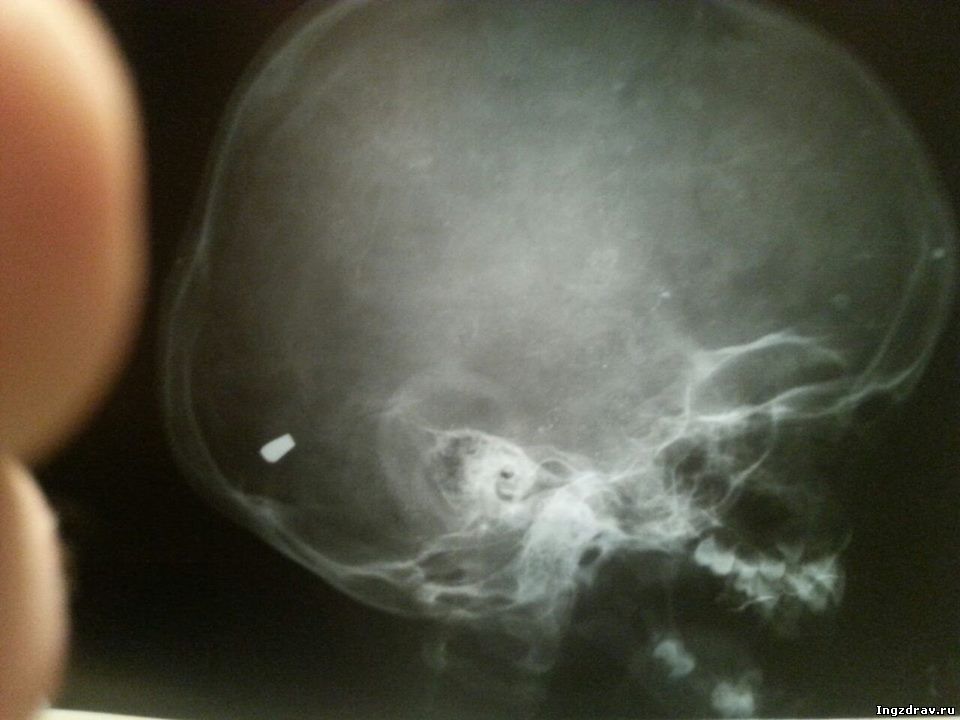

01:42 21 сентября 2014 года в МЦРБ в голове ребенка была обнаружена пуля |

21 сентября 2014 года в Малгобекскую ЦРБ доставили 5-летнего ребенка с ушибленной раной волосистой части головы, однако, после рентген-снимка, в голове ребенка была обнаружена пуля. Позже выяснилось, что шальная пуля попала мальчику в голову в результате беспорядочной стрельбы на одной из свадеб. информация Мага Хамхо |